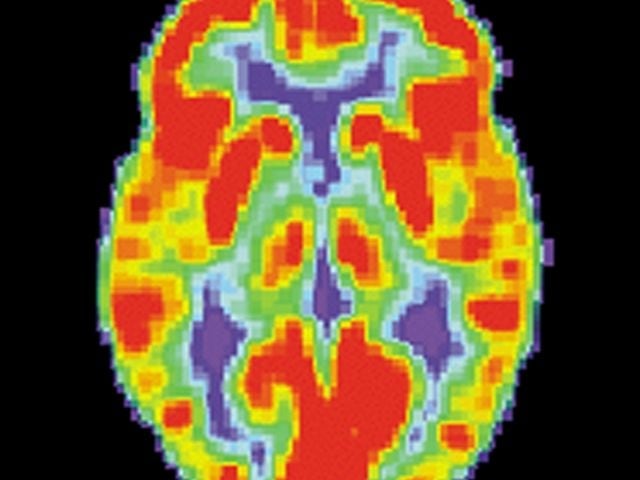

Para ello, la investigación ha tomado en cuenta a más de 2.000 adolescentes, quienes han sido reclutados a partir de los 14 años y se les ha dado seguimiento durante cinco años. Durante este tiempo se les han hecho resonancias magnéticas y otros análisis que revelan imágenes del cerebro.

Para el análisis particular (el publicado este miércoles) se utilizó la información de 682 jóvenes. De ellos, además de las imágenes cerebrales, también se tomaron en cuenta entrevistas y pruebas psicológicas.

¿Qué determinaron investigadores? Según el estudio, los científicos notaron cambios en el volumen de dos zonas específicas del cerebro: el putamen y el núcleo caudado. Ambas estructuras forman el llamado cuerpo estriado.

Dentro de sus funciones, el cuerpo estríado se encarga de regular la memoria operativa, la focalización de la atención, la regulación de las conductas y la selección de acciones en torno a la recompensa esperada por una acción.

Las anomalías en esta parte del cerebro están relacionadas con condiciones como la depresión, la ansiedad, el trastorno bipolar, el trastorno obsesivo-compulsivo y las adicciones.

De acuerdo con los investigadores, esto podría explicar por qué los trastornos de ansiedad y depresión son más comunes en las víctimas de bullying.

“Aunque a la hora de diagnosticar ansiedad no siempre se consideran los cambios estructurales en el putamen y núcleo caudado, sí es necesario saber esto porque también impacta en otras esferas, como la motivación de la persona, su atención y el procesamiento de sus emociones”, explicó en un comunicado de prensa Burke Quinlan, uno de los investigadores.